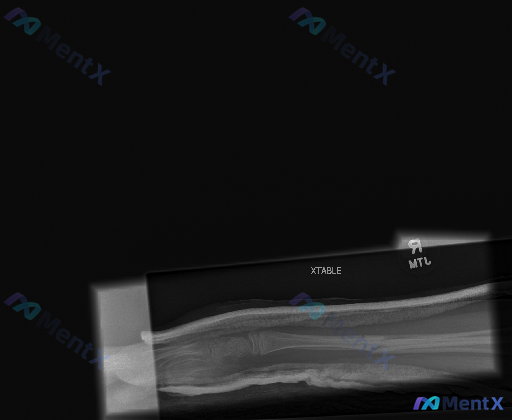

整理到一张儿童/青少年前臂侧位X光的影像资料,先和大家同步已有的客观影像学观察: 影像所见(不含诊断) 1. 骨骼与定位:前臂侧位投影,桡骨在掌侧、尺骨在背侧,周围可见石膏外固定的条带状致密影;包含远端前臂及部分腕关节,肘关节未在视野内。 2. 骨折相关表现: - 尺骨远端干骺端/骨干交界处可见皮质...